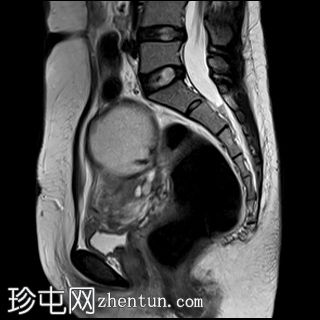

矢状位

7.jpg

T2加权像

子宫后壁子宫圆锥增厚,累及直肠前壁。

子宫、双侧卵巢和直肠因挛缩性粘连/纤维带而靠近,形成近期描述的深部盆腔子宫内膜异位症的“三叶草征”。

双侧卵巢出血性囊肿提示双侧子宫内膜异位囊肿,也称为巧克力囊肿。双侧卵巢位置接近,被称为“接吻卵巢”,这是由于粘连、子宫圆锥韧带和卵巢圆韧带增厚以及卵巢、直肠和子宫呈三叶草状排列所致,提示盆腔子宫内膜异位症。